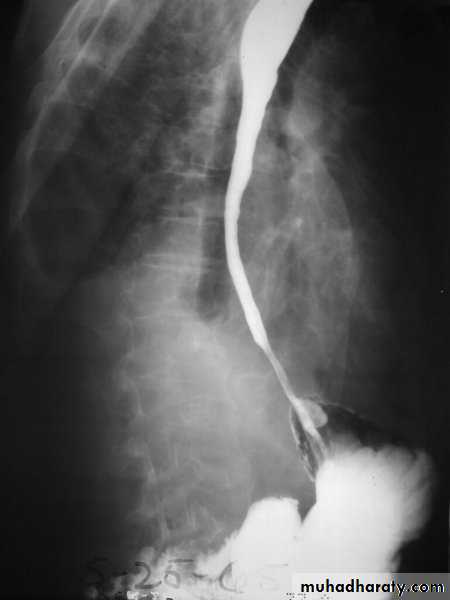

Investigations Chest X-ray; widening of the mediastinum, aspiration pneumonia.A barium swallow; tapered narrowing of the lower esophagus, esophageal body is dilated, aperistaltic and food-filled.Endoscopy; must always be carried out, carcinoma of the cardia can mimic the presentation and radiological and manometric features of achalasia ('pseudo-achalasia').Manometry; confirms the high-pressure, non-relaxing lower esophageal sphincter with poor contractility of the esophageal body.

Investigations Endoscopy; The investigation of choice, with cytology and biopsy.Barium swallow ; site and length of the stricture .Thoracic and abdominal CT Endoscopic ultrasound (EUS)